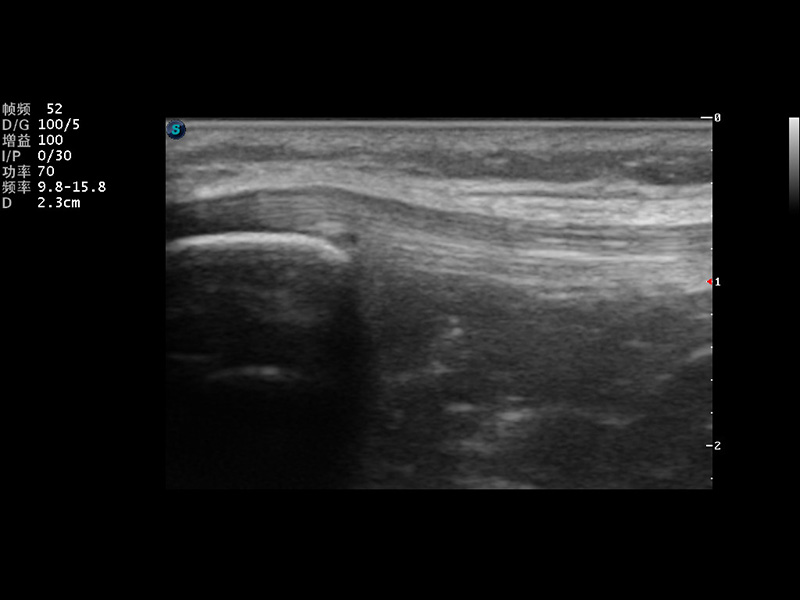

S9便携式彩色多普勒超声诊断仪是云顶集团官网研发的高端便携彩超设备,外观设计新颖、产品性能卓越。S9在便携超声领域采用了突破传统的触摸屏交互设计,并以先进的软件硬件技术和设计理念,为您带来清晰的图像质量、稳定的工作性能和便捷的操作体验。